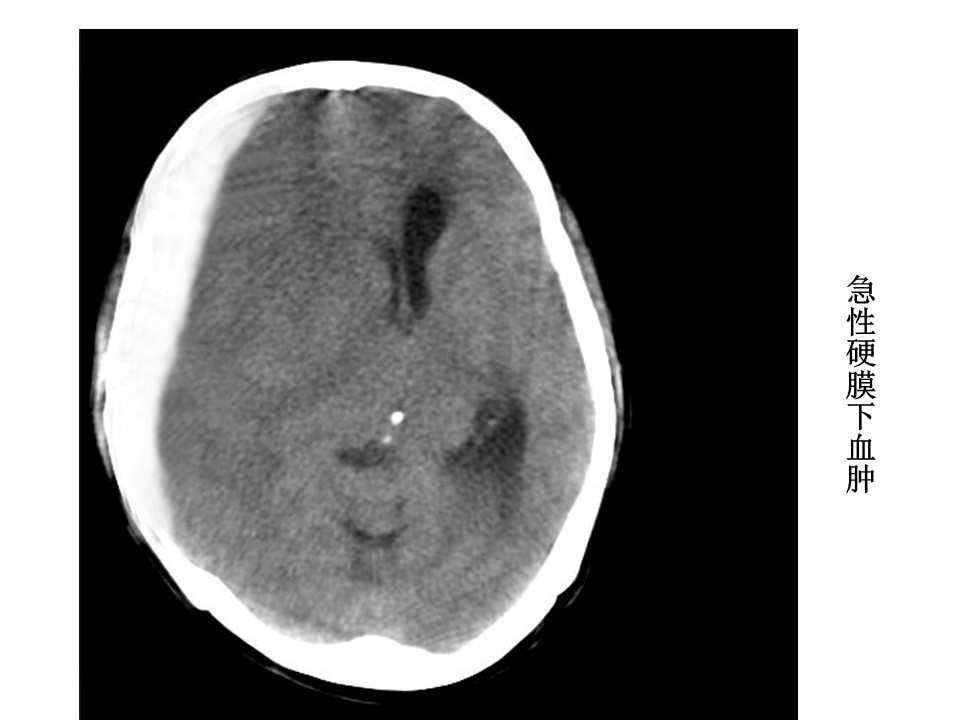

“头颅CT解剖及诊断PPT” 的相关文章